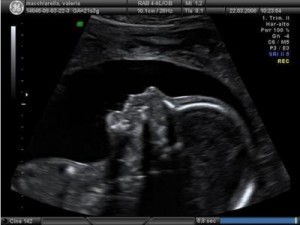

L'ecografia morfologica (sia in 3D che in 4D) può essere eseguita circa a metà del secondo trimestre ed è consigliabile inserirla nelle visite del secondo trimestre di gravidanza.

La morfologica, insieme alla prima ecografia di inizio gravidanza, è uno degli esami più importanti da fare durante la gravidanza perché permette di controllare con accuratezza a che punto della gestazione sei e, soprattutto, di verificare la morfologia del feto ed escludere eventuali malformazioni. Normalmente si effettua a metà del secondo trimestre perché è questo il momento in cui il bambino è nelle migliori condizioni per essere studiato, dato il rapporto ottimale tra la quantità di liquido amniotico e la dimensione del feto.

L'ecografia morfologica permette la valutazione delle dimensioni del feto (biometria fetale), dell'impianto e della struttura della placenta, della quantità di liquido amniotico presente nell'addome, dello stato in cui si trova il collo dell'utero, ma fornisce soprattutto uno studio analitico di tutti i distretti anatomici esplorabili nel feto che, a questo punto della gravidanza, è già molto formato. Solitamente, nel corso dell'esame morfologico, è abitudine effettuare anche l'esame dell'ecodoppler, ovvero la valutazione del flusso sanguigno fra la placenta e il feto attraverso il cordone ombelicale per determinare la presenza di eventuali difetti placentari.